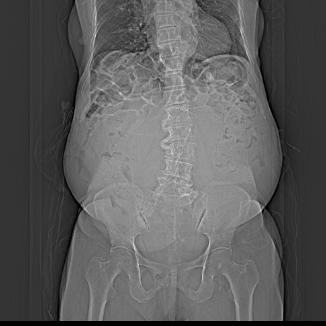

95岁的王奶奶腹部明显憋胀如篮球,一个月来反复尿频,尿急,种种症状让王奶奶苦不堪言,家人见此状也焦急万分,送王奶奶到市二医院,妇产科副主任林苑医师体查发现患者的腹部有囊性包块,上界达剑突下。进一步完善相关检查,医学影像显示:腹腔内巨大占位性病变,几乎占据了盆腔的全部空间!内部分小房呈密度增高,考虑卵巢粘液性囊腺瘤。

林苑主任与钟红珠主任在术中探查发现囊肿约36X34X30cm,肿瘤呈多囊性,表面与乙状结肠及肠管系膜广泛黏连,黏连致密。肿瘤予针头穿刺减压吸出囊液,囊液液体呈浅褐色,囊内液约5000ml。